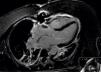

The patient's clinical evolution was favorable, however the LV dysfunction, wall motion abnormalities and AV conduction abnormalities did not improve significantly during the week after admission. Troponin level was maximum at admission (0.79ng/ml). Due to the lack of LV function improvement a temporary coronary occlusion could not be ruled out as the cause of apical ballooning. To better clarify the diagnosis cardiac magnetic resonance imaging was performed, almost two weeks after admission, and showed global (ejection fraction: 50%) and regional (hypokinesis of the 17th segment, lateral and inferior apical segments) improvement of LV function. There was no apical thrombus or delayed enhancement, consistent with the diagnosis of TC (Figure 4).